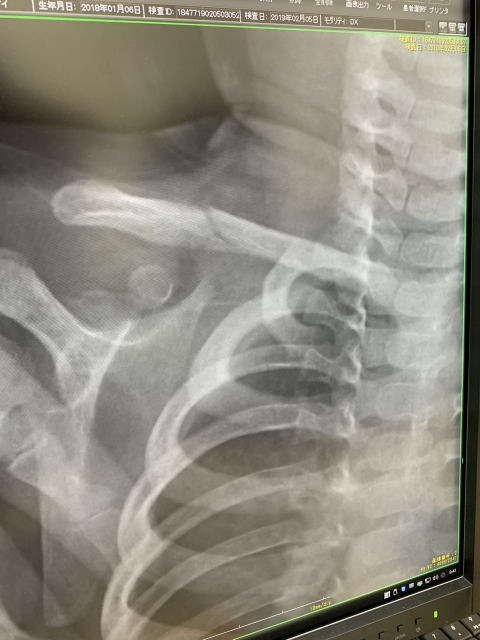

鎖骨骨折の治療 鎖骨骨折の治療法は保存療法と手術療法に分けられます。 保存療法 鎖骨骨折は比較的予後が良好であるため、多くは保存療法が選択されます。 骨の転移が大きくな

鎖骨骨折 一般社団法人 日本骨折治療学会